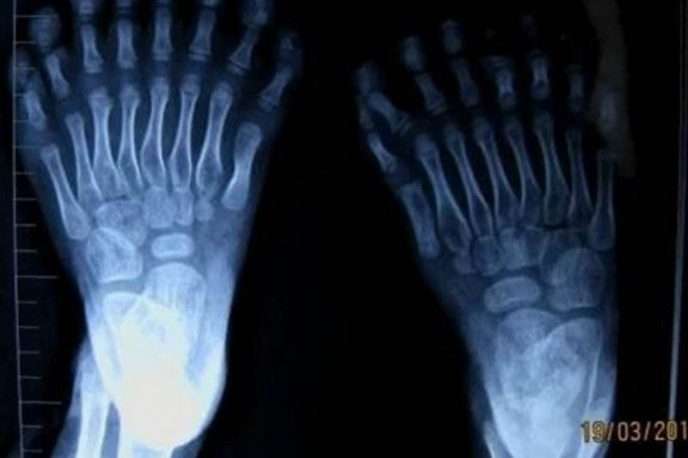

Այս լուսանկարները կարող են ապշեցնել յուրաքանչյուրին։ Արդյո՞ք սա ֆոտոշոփ է։ Ահա թե այս լուսանկարներից որոնք են իրական, իսկ որոնք են ֆոտոշոփի մասնագետի աշխատանք։